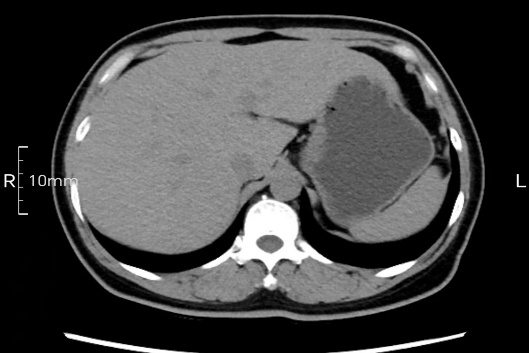

看看下面三幅便知遵醫(yī)囑的重要性。

沒(méi)禁食,胃內(nèi)全是食物,導(dǎo)致胃壁顯示不清。

禁食但檢查前沒(méi)有喝飽,胃未能漲開(kāi),胃壁觀察效果不佳。

完美禁食且喝飽飽,胃壁完美展現(xiàn)。